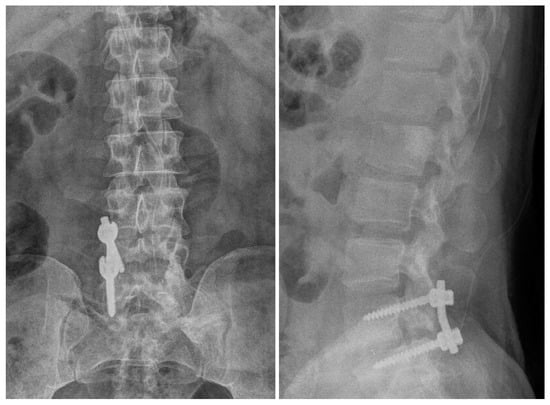

2.1. Case 1